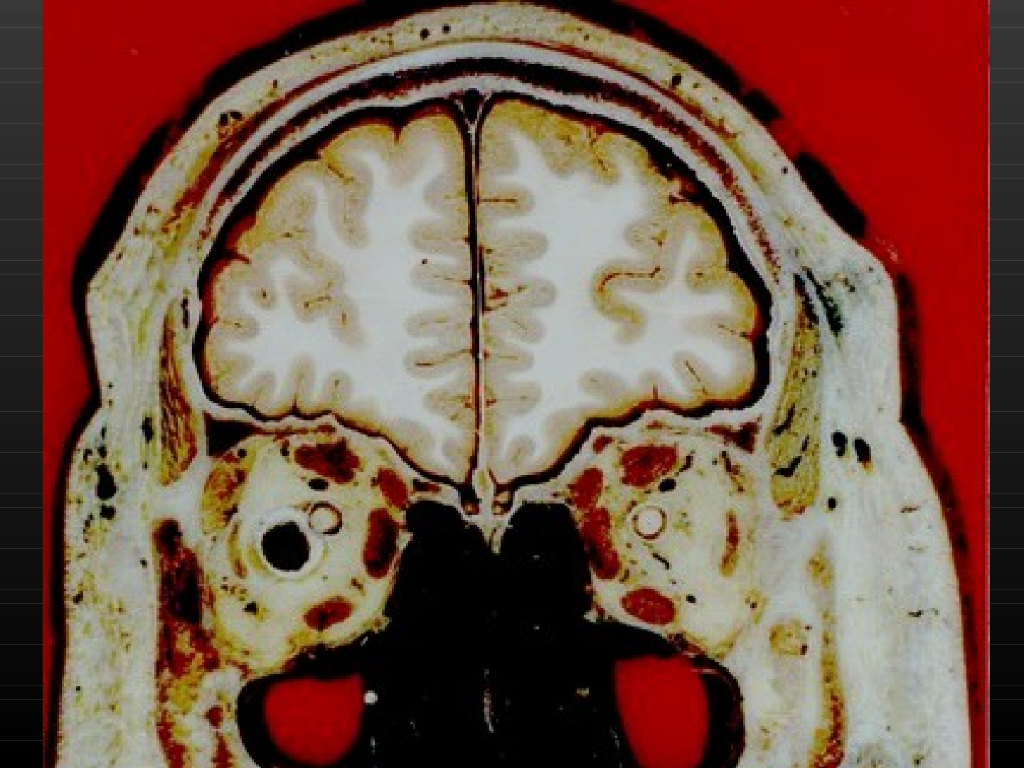

《断层影像解剖学》演示文稿-头部冠状断层解剖与MRI.pdf